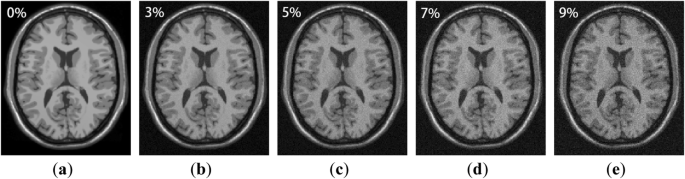

The experimental data in this part was downloaded from the BrainWeb [26]. We downloaded the T1-weighted brain MR images which are corrupted with 0, 3, 5, 7, and 9% of Rician noise, and the MR image size is 181 × 217 × 181 voxels with 1 mm slice thickness. Different level of noisy MR images are shown in Fig. 1.

Since the naked eye cannot distinguish the difference of noise levels very well, we used colormap to dye the images. As shown in Fig. 2, we can clearly see that as the noise level increases, the boundaries of the MR images became more and more blurred, and some structural details have been lost. So it is necessary to remove the noise in MR images.